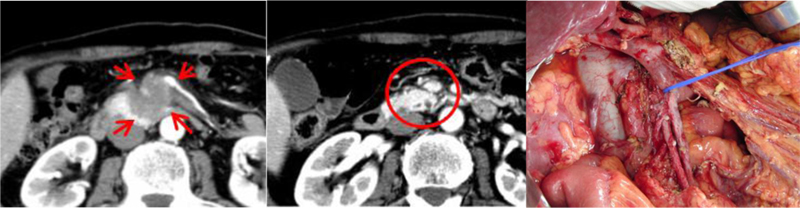

Multidisciplinary Therapies for Locally Advanced Unresectable Pancreatic Cancer

We are committed to "never giving up on treatment" in our approach to pancreatic cancer. Even when a patient is diagnosed with locally advanced unresectable cancer, we pursue every possible treatment option through multidisciplinary therapies, always striving for the possibility of resection. In cases of advanced pancreatic cancer where the tumor has invaded the major arteries around the pancreas, making surgery difficult, we actively combine chemotherapy and heavy ion therapy to reduce the tumor size. As a result, we are seeing an increasing number of cases where patients initially diagnosed as unresectable become candidates for surgery (Conversion Surgery). We are fully dedicated to the treatment of our patients, envisioning the day they overcome cancer.

pancreatic body cancer invading the celiac artery